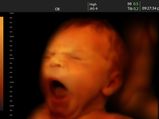

కడుపులోని బిడ్డకు స్కానింగ్ వల్ల కలిగే డేంజరస్ సైడ్ ఎఫెక్ట్స్

గర్భాశయంలో బేబీ.. చేసే ఆశ్చర్యకర విషయాలు